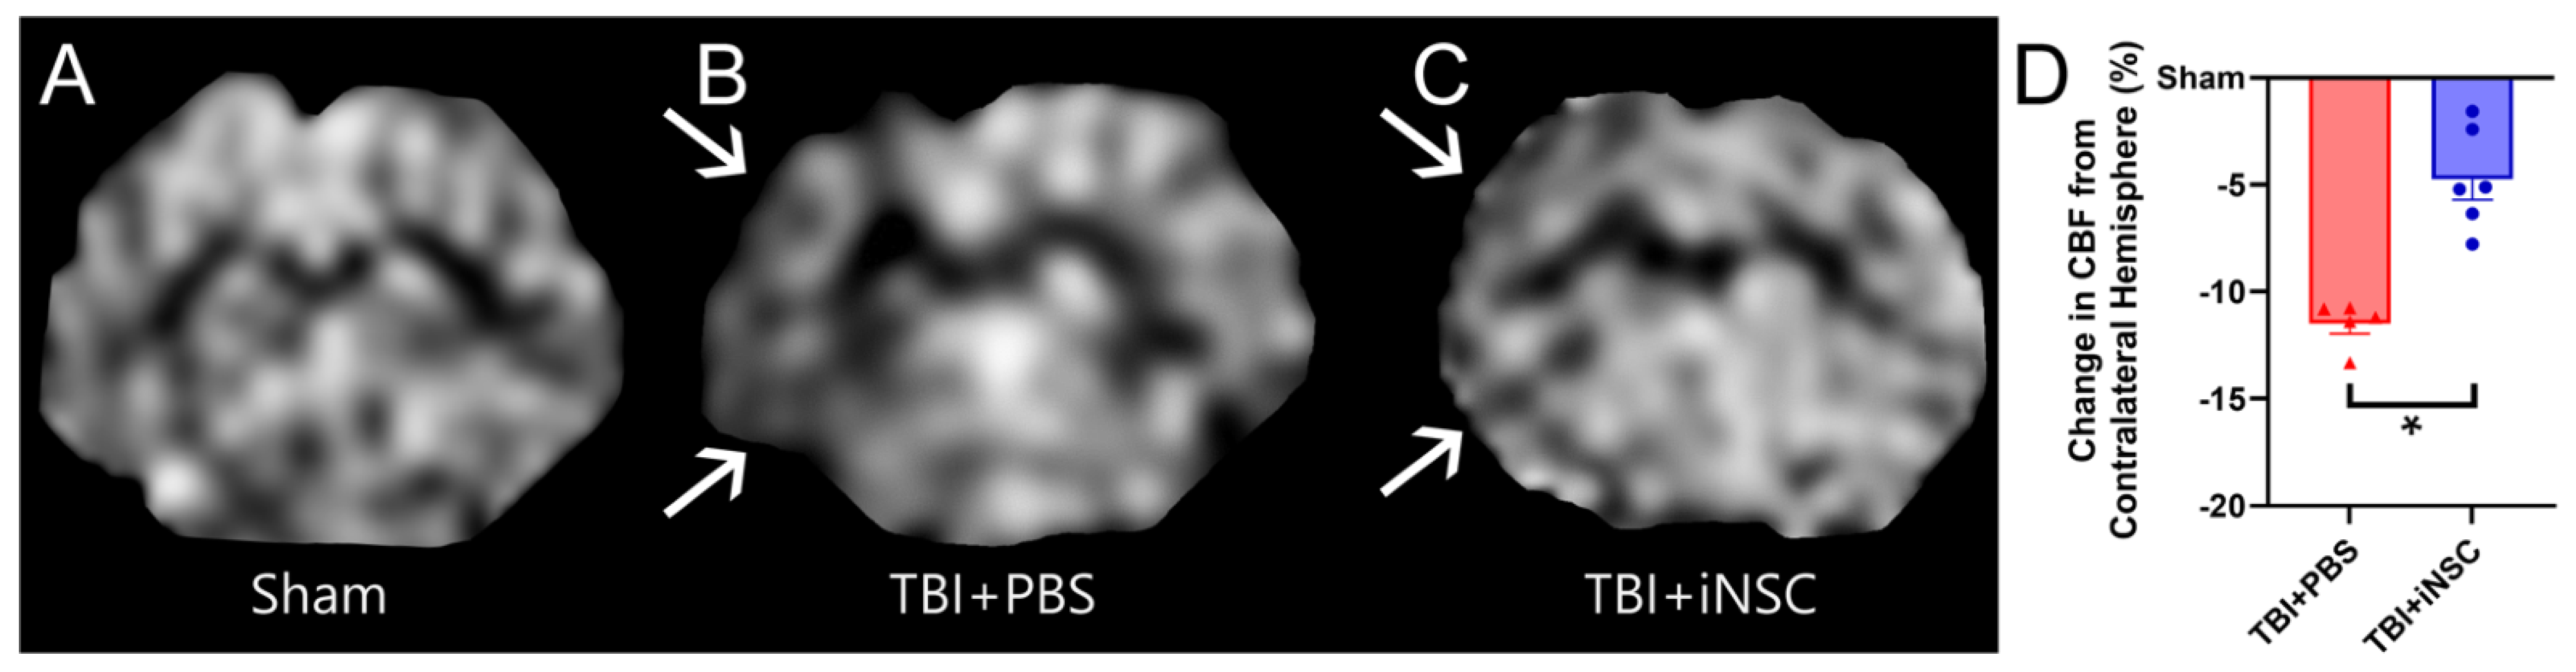

3.4. iNSC Transplantation Significantly Decreased Ipsilateral Atrophy, Lesion Volume, and Midline Shift While Preserving Cerebral Blood Flow